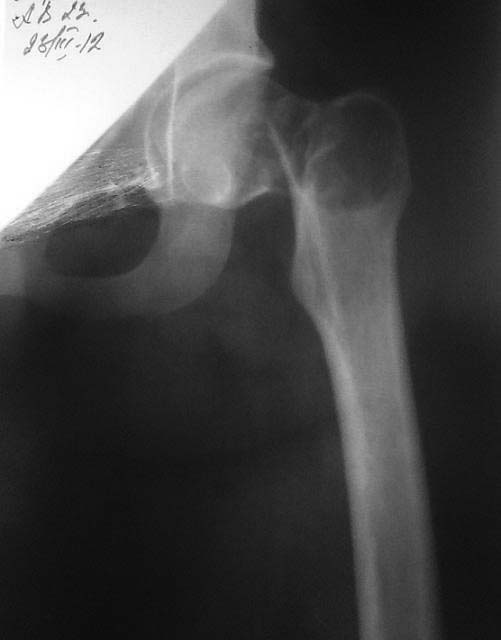

[Ortho] Патологический перелом шейки бедра

Пациентка 23 года срок беременности 22 недели. Травма низкоэнергетическая ( падение на бок ). Отмечает наличие болевого синдрома в области т/б сустава около 1 года. Планируем остеосинтез (гамма стержнем или  DHS)  + биопсия.

Ув. коллеги помогите определиться с тактикой. Возможно мы что то не учитываем.